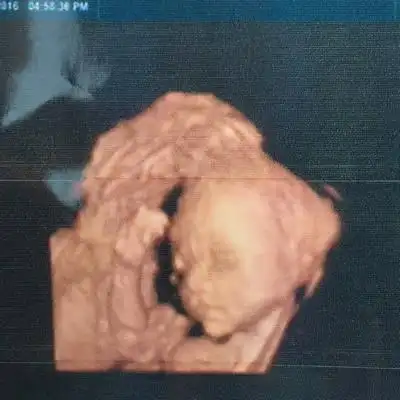

大家帮忙看一下是兔唇吗?